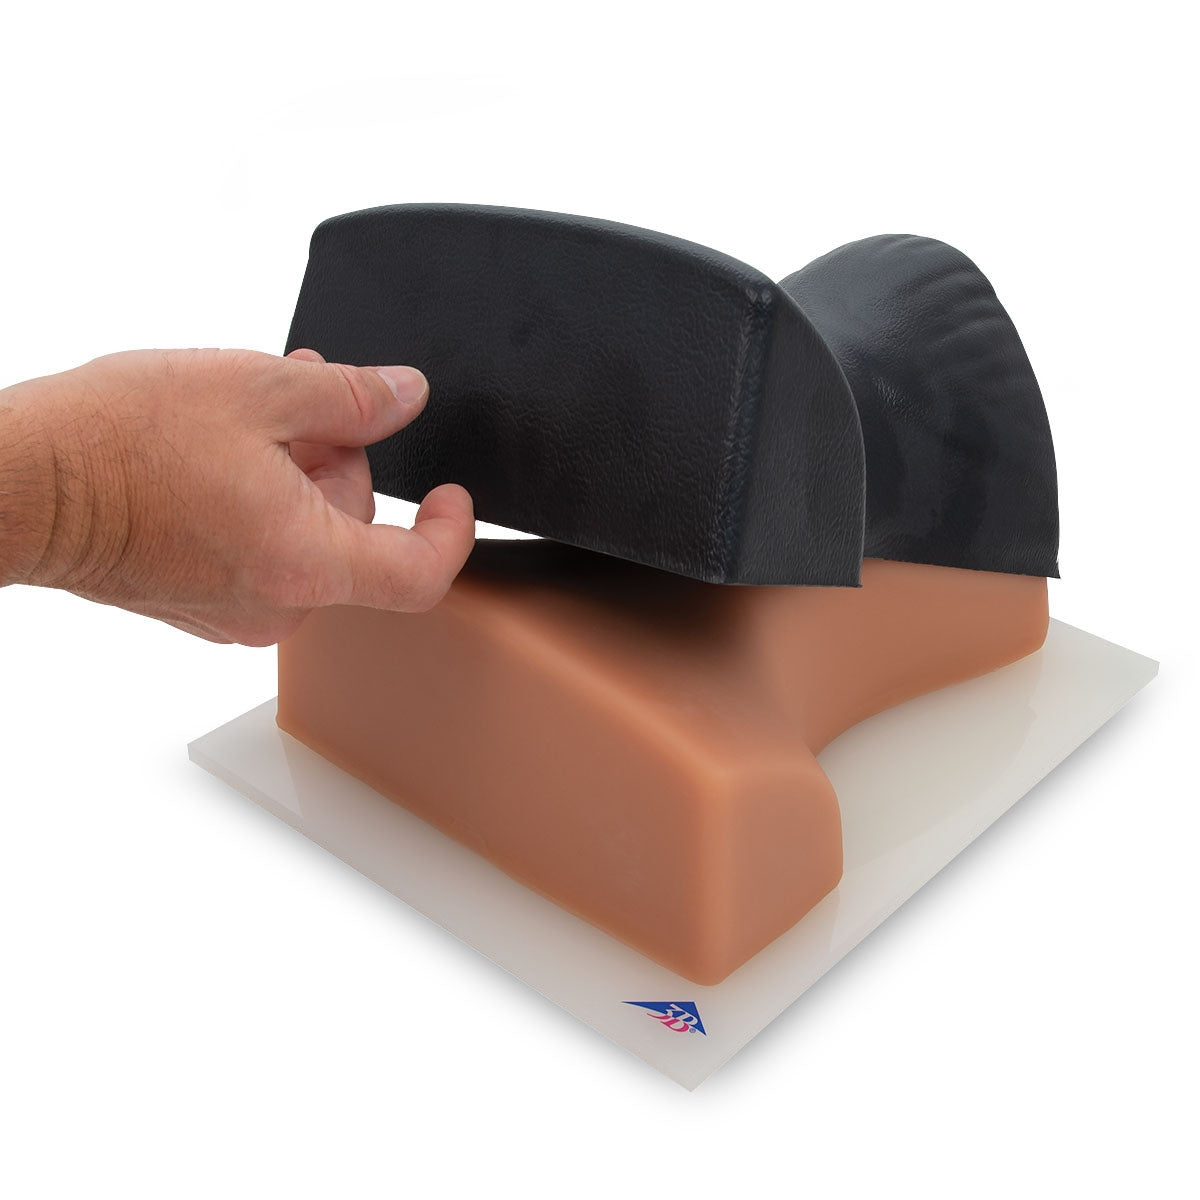

Geriatric LOR Insert (2) for Epidural and Spinal Injection Trainer

Geriatric LOR Insert for Epidural and Spinal Injection Trainer

Replacement Skin for Epidural and Spinal Injection Trainer

Standard LOR Kit (2) for Epidural and Spinal Injection Trainer

Our range of epidural injection trainers includes detailed anatomical models that replicate the lumbar and thoracic spine, providing a hands-on learning experience for anaesthetists, medical students, and pain management specialists. These advanced simulators allow users to practise needle placement, identify key anatomical landmarks, and develop proficiency in administering epidural and spinal anaesthesia with confidence. Ideal for medical schools, hospitals, and professional training programmes, these epidural trainers support skill development in regional anaesthesia, labour pain management, and spinal procedures. With lifelike materials that simulate real patient responses, our models offer a realistic and immersive training experience.